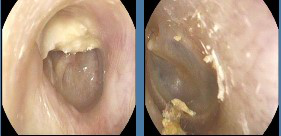

耳內鏡下見:右側松弛部內陷,上鼓室膽脂瘤